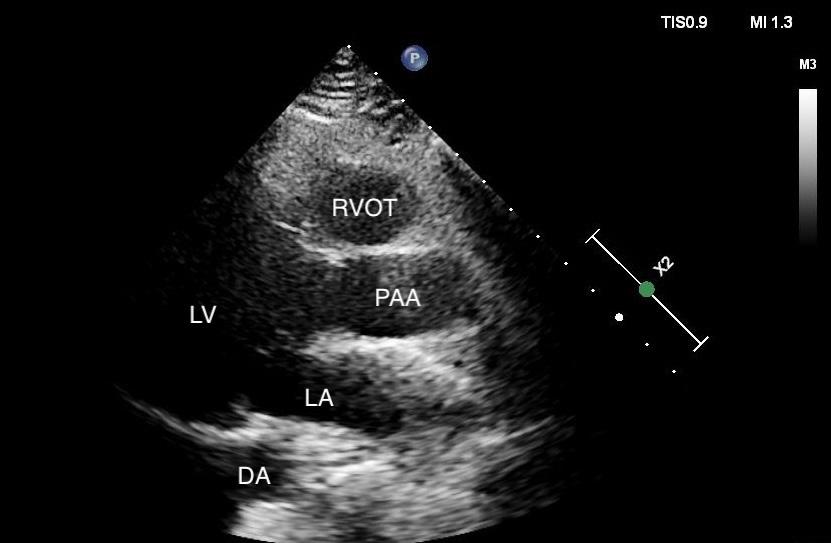

In the case covered in this article, an 85-year-old man with septic shock caused by a perforated sigmoid colon was profoundly hypovolemic and required crystalloid resuscitation and dual vasopressors. Ultrasound revealed that his internal jugular vessels were completely collapsible. Initial attempts to place the catheter were unsuccessful due to vessel collapse. The Trendelenburg position did not adequately dilate the internal jugular vein, as shown in Image 1. However, using a passive leg raise, significant dilation of the internal jugular vein was observed, enabling successful cannulation (Image 2).